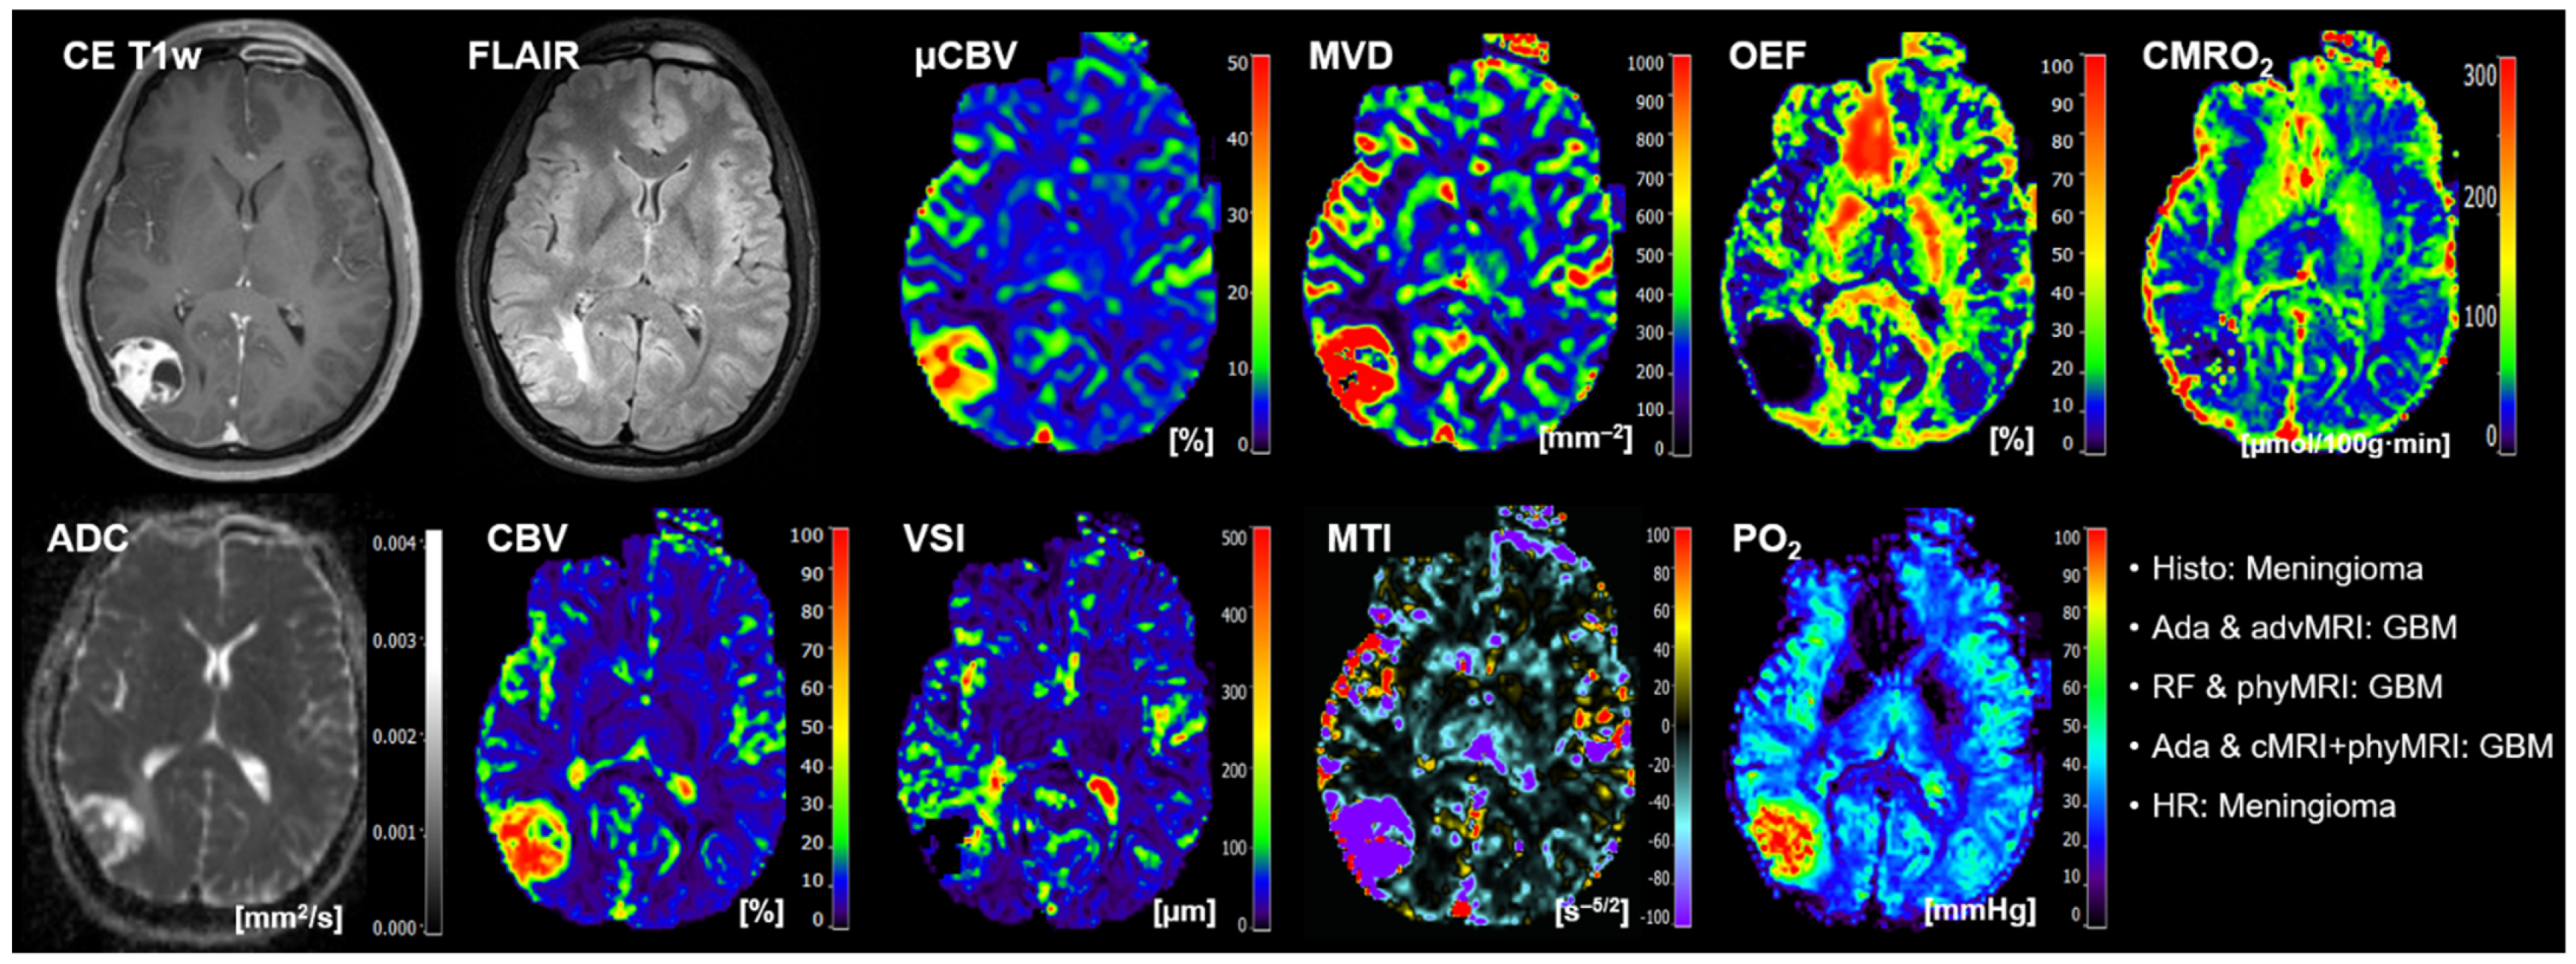

- The conventional anatomical MRI (cMRI) protocol for clinical routine diagnosis of brain tumors included, among others, an axial fluid-attenuated inversion recovery (FLAIR) sequence as well as a high-resolution contrast-enhanced T1-weighted (CE T1w) sequence.

- The advanced MRI (advMRI) protocol for clinical routine diagnosis of brain tumors was extended by axial diffusion-weighted imaging (DWI; b values 0 and 1000 s/mm2) sequence and a gradient echo dynamic susceptibility contrast (GE-DSC) perfusion MRI sequence, which was performed using 60 dynamic measurements during administration of 0.1 mmol/kg-bodyweight gadoterate-meglumine (Dotarem, Guerbet, Aulnay-Sous-Bois, France).

- The physiological MRI (phyMRI) protocol included the innovative MRI techniques of vascular architecture mapping (VAM) [31] for the assessment of microvascular architecture and neovascularization activity, as well as the quantitative blood-oxygenation-level-dependent (qBOLD) imaging approach [19,32] for assessment of tissue oxygen metabolism and tension. The VAM approach [33,34] additionally required a spin-echo DSC (SE-DSC) perfusion MRI sequence conducted with the same parameters and contrast agent injection protocol as described for the routine GE-DSC perfusion MRI. Details of our strategy to minimize adverse effects due to differences in time to first-pass peak and contrast-agent leakage, which could significantly affect the data evaluation, were previously described [33,34]. The qBOLD approach [19,32] additionally required a multi-echo GE sequence and a multi-echo SE sequence for the mapping of the transverse relaxation rates R2* (=1/T2*) and R2 (=1/T2), respectively. All phyMRI sequences for VAM and qBOLD were carried out with identical geometric parameters (voxel size, number of slices, etc.) and slice position as used for the routine GE-DSC perfusion sequence. The phyMRI protocol required seven minutes of extra scan time in total.